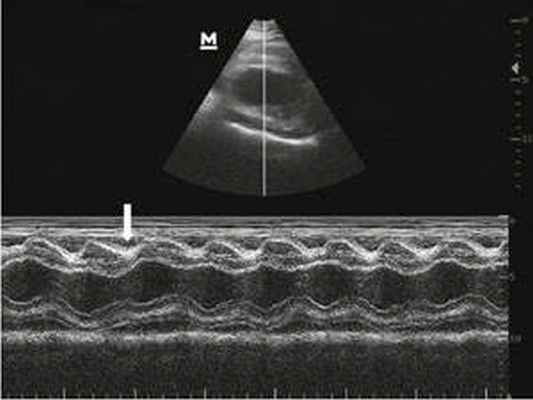

Эхокардиография (УЗИ сердца) — это наиболее информативный метод, позволяющий оценить объём жидкости в перикарде, уменьшение объёмов полости правого предсердия и правого желудочка при наполнении кровью и другие признаки, которые сможет интерпретировать только врач.

![УЗИ сердца [13]](/pimg1/tamponada-serdtsa-prichini-78B002.jpeg)

Эхокардиография при тампонаде сердца имеет наиболее высокую диагностическую ценность, так как позволяет обнаружить даже небольшой объем выпота в полости перикарда, а также наличие диастолического коллапса правых камер сердца и изменение скорости кровотока через трикуспидальный и митральный клапаны на вдохе. Чреспищеводная ЭхоКГ проводится при появлении признаков тампонады после хирургического вмешательства на сердце, при трудностях выявления перикардиального выпота.